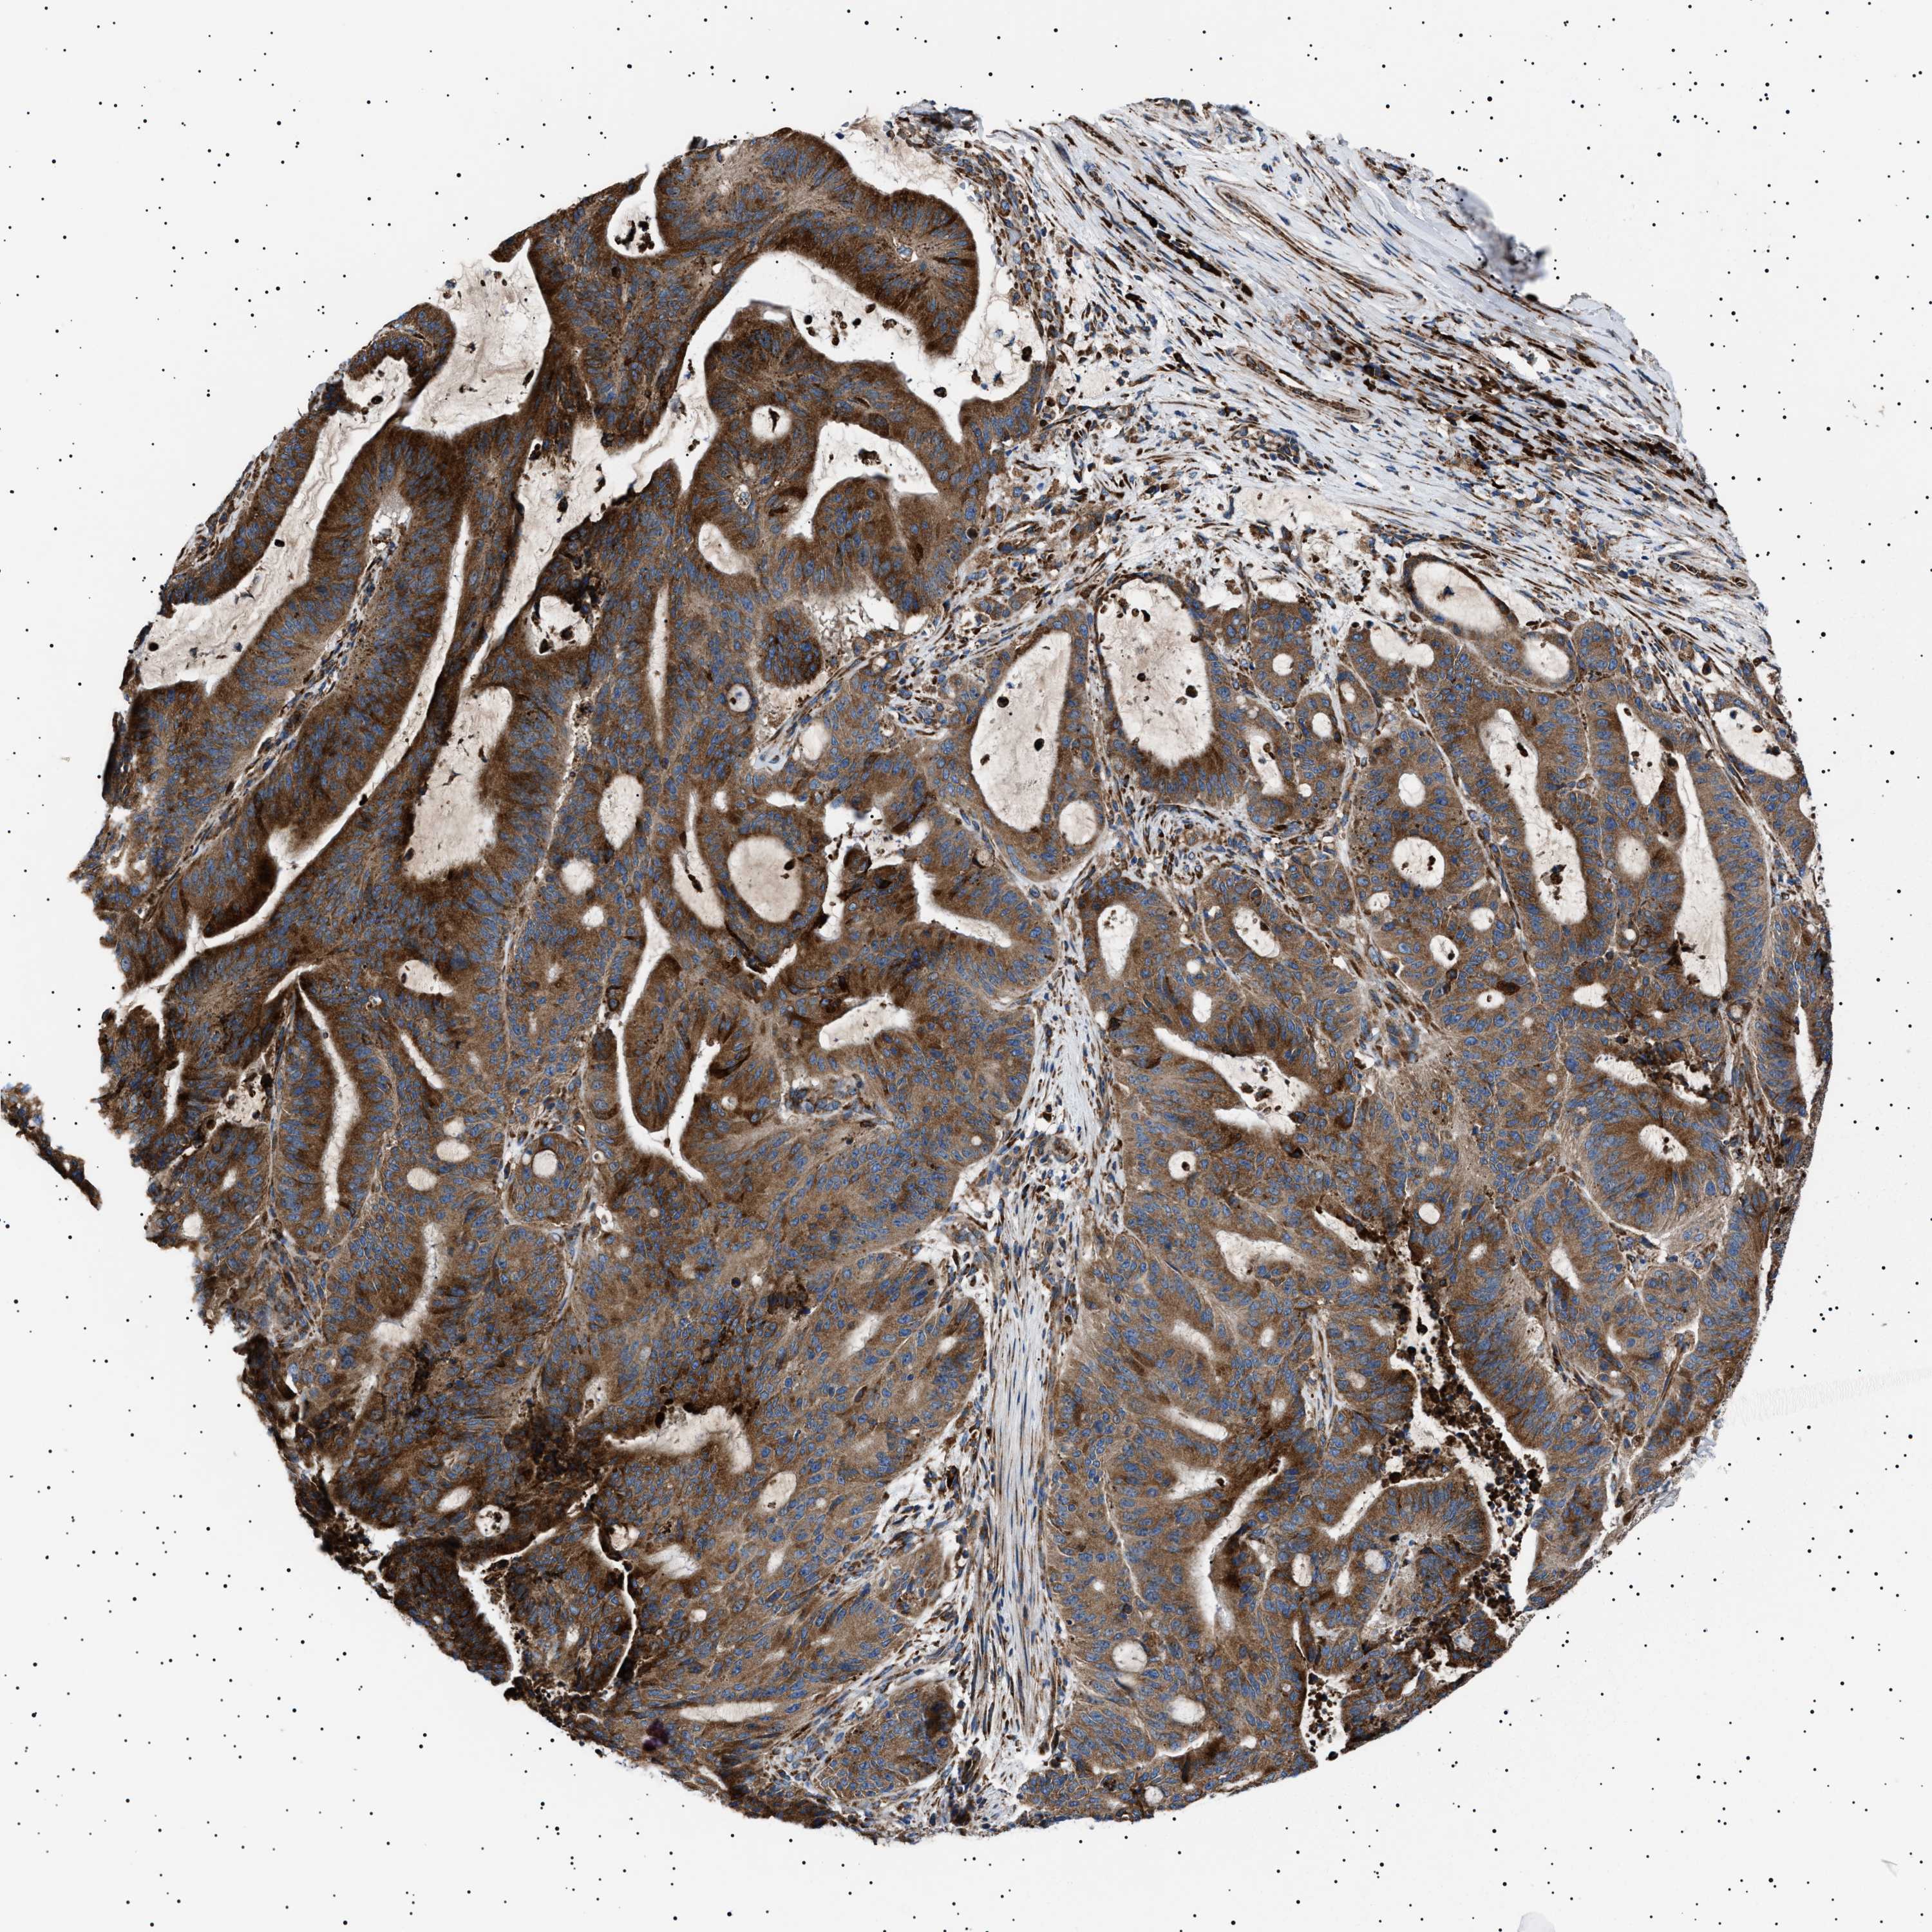

LIVER CANCER - Protein expressioni

A mouse-over function shows sample information and annotation data. Click on an image to view it in a full screen mode. Samples can be filtered based on level of antibody staining by selecting one or several of the following categories: high, medium, low and not detected. The assay and annotation is described here.

Note that samples used for immunohistochemistry by the Human Protein Atlas do not correspond to samples in the TCGA dataset.

Antibody stainingi

Antibody staining in the annotated cell types in the current human tissue is reported as not detected, low, medium, or high, based on conventional immunohistochemistry profiling in selected tissues. This score is based on the combination of the staining intensity and fraction of stained cells.

Each image is clickable and will lead to virtual microscopy that enables deeper exploration of all samples and also displays staining intensity scores, fraction scores and subcellular localization as well as patient and tissue information for each sample.

Antibody HPA001915

Antibody HPA021542

Staining

High

Medium

Low

Not detected

Intensity

Strong

Moderate

Weak

Negative

Quantity

>75%

75%-25%

<25%

None

Location

Nuclear

Cytoplasmic/membranous

Cytoplasmic/membranous,nuclear

Cholangiocarcinoma

Carcinoma, Hepatocellular, NOS